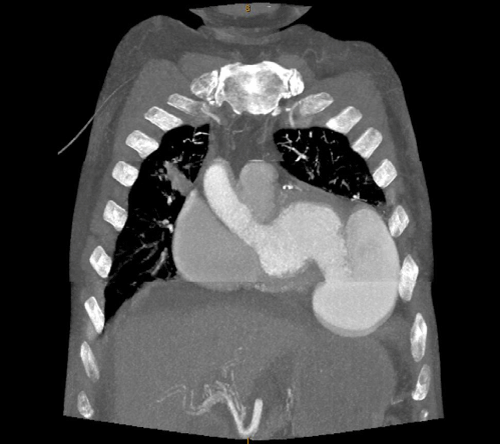

Delayed Rupture of Left Ventricular Aneurysm with Resultant Coexisting Pseudoaneurysm

Shwe Yee Oo1, Adel Ekladious2* and Yee Phyo Hein2

A 60 year old gentleman was transferred to a regional hospital following an admission for non-ST elevation myocardial infarction (NSTEMI) complicated by true left ventricular apical aneurysm and pyopericardium...